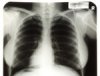

Рентгеновские снимки грудной клетки Мэрилин Монро были проданы на аукционе Hollywood Legends в Лас-Вегасе за 45 тысяч долларов, сообщает Associated Press. Торги проходили в выходные, 26 и 27 июня. Несколько рентгеновских снимков были сделаны в 1954 году, когда Монро поступила в медицинский центр Cedars of Lebanon Hospital во Флориде с диагнозом эндометриоз. Весной 2010 года аукционный дом Julien's объявил о том, что снимки будут проданы в рамках аукциона вещей, связанных с именами голливудских актрис. Ожидалось, что максимальная стоимость рентгена грудной клетки Мэрили Монро не превысит трех тысяч долларов. Среди прочих вещей, проданных на аукционе в Лас-Вегасе, также оказалось кресло, фигурировавшее в последней фотосессии Монро для журнала Life Magazine. Этот предмет мебели ушел с молотка за 35 тысяч долларов.